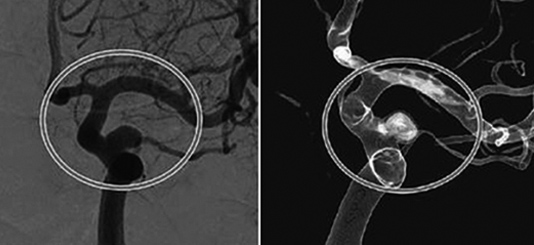

뇌동맥류 색전술 |